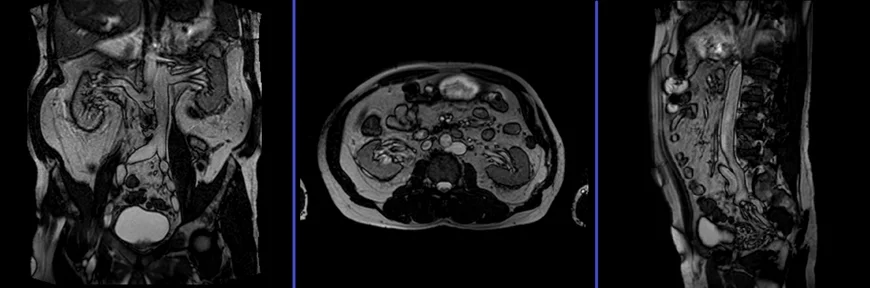

MRI Kidney Ureters and Bladder (KUB) Localizer

A three-plane T2 TRIFISP\HASTE localizer must be taken initially to localize and plan the sequences. These are fast single-shot localizers with under 25s acquisition time, which are excellent for localizing vascular structures. Take at least 5-8 slices in all planes to get the best results.

T2 HASTE\TRUFI axial 4 mm

Plan the axial slices on the coronal plane, angle the positioning block parallel to the right and left iliac crest. Check the positioning block in the other two planes. An appropriate angle must be given in the sagittal plane (horizontally across the abdomen). The slices must be sufficient to cover the entire abdomen and pelvis from the diaphragm down to the symphysis pubis. Use a field of view (FOV) that is large enough to encompass the entire abdomen, typically ranging from 350mm to 400mm.

T1 vibe DIXON 3d axial 4 mm

Plan the axial slices on the coronal plane; angle the position block parallel to the line along the right and left iliac crest. Check the positioning block in the other two planes. An appropriate angle must be given in the sagittal plane (perpendicular to the lumbar spine). Slices must be sufficient to cover the whole abdomen and pelvis from diaphragm down to symphysis pubis. FOV must be big enough to cover the whole abdomen (normally 350mm-400mm).

T1 vibe DIXON 3D coronal 2mm

Plan the coronal slices on the axial plane; angle the position block parallel to the mid line along the right and left kidneys. Check the positioning block in the other two planes. An appropriate angle must be given in the sagittal plane (parallel to L spine). Slices must be sufficient to cover the whole urinary system. Phase oversampling and, in the case of 3D blocks, slice oversample, must be used to avoid wrap around artefacts. FOV must be big enough to cover the kidneys and bladder. Instruct the patient to hold their breath during image acquisition. (In our department we instruct the patients to breath in and out twice before the “breath in and hold” instruction.).

T2 HASTE fat sat coronal 3mm